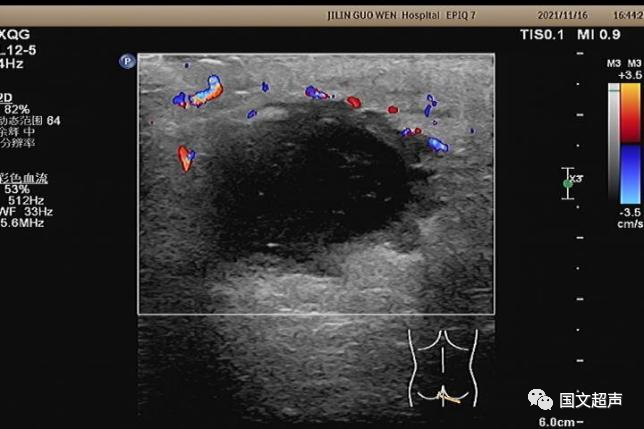

超聲檢查所見:

肛周:7點鐘方向皮下脂肪層內(nèi)探及不均質低無回聲包塊,范圍約4.6*3.0cm,較淺處距體表約0.6cm,邊界不清,周圍軟組織回聲增強,CDFI:周邊血流信號豐富,輕加壓探頭有涌動感,如下圖: